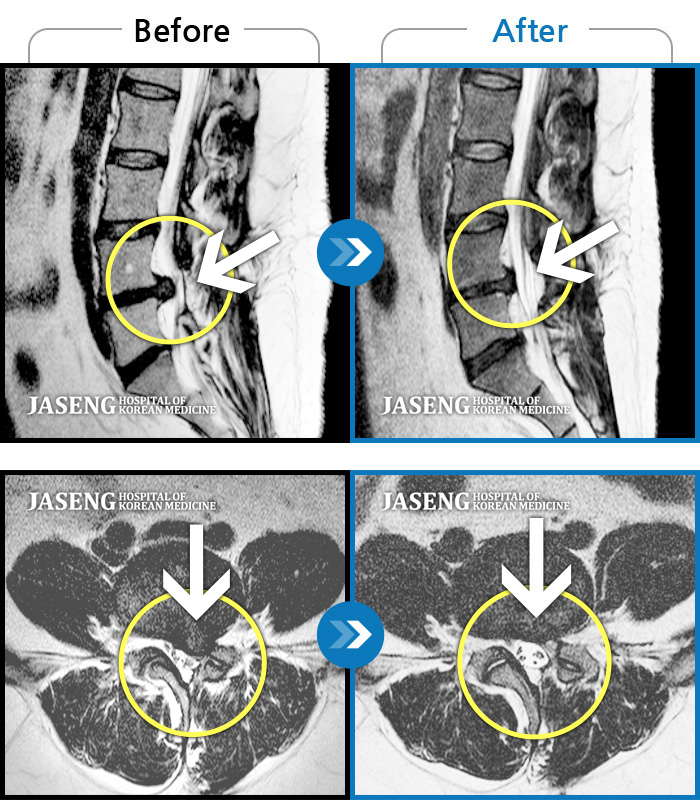

허리디스크

인천 · 조남훈 원장

좌측 허벅지와 종아리가 찌릿하고 묵직한 통증이 있어요.

촬영시기

2025.03.18 ~ 2025.07.22

2025.08.01

조회수 14,275